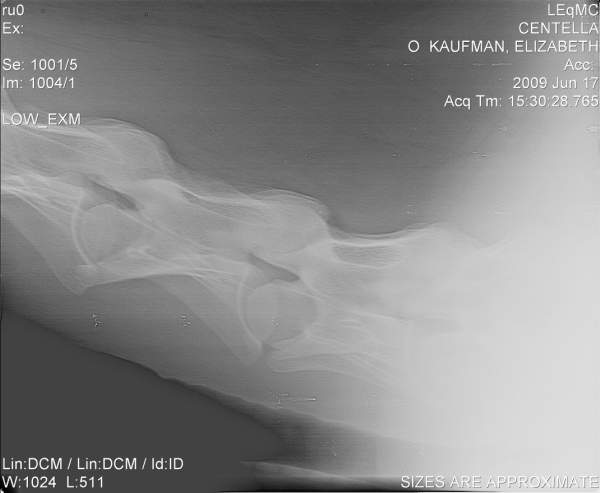

Posted on Thursday, Jun 18, 2009 - 12:01 pm: Hello DrO,I'd be curious to hear your opinion of these cervical radiographs. They are of a 7 yo horse with a history of non-performance with various low grade hind end lamenesses and symmetric poor muscle development. The neuro exam on this horse was "not quite right" on the hind end, though there were no glaring, repeatable failures.

Posted on Friday, Jun 19, 2009 - 8:15 am: Hello elk,Of all skeletal radiographs cervical vertebral radiographs are some of the very hardest to accurately interpret requiring the very best resolution, often over an hour of review with rulers, marking pens, and calculators to determine the significance of perceived irregularities. In the above images many of the facets and spinal canal spaces are not clear enough for a good evaluation. They may be fine on the orignals however. So let me turn this around and ask you did the folks reviewing the originals and hopefully spend the required time to assess the hundreds of individual points of interest in such a radiographic series find any abnormalities? I always think it wise to have such a set of radiographs with questionable findings be reviewed by a equine radiologist or orthopedic surgeon. DrO |

Posted on Friday, Jun 19, 2009 - 9:37 am: Hello DrO,The x-rays were reviewed as carefully as possible, I believe, given the experience and schedules of the folks involved. The originals are somewhat more clear, though not perfect-- it's a very big horse. Conversion to jpeg format and reduction for posting has not improved them! These x-rays also have been referred out for review. The equine surgeon who examined the horse and (with her colleagues) reviewed the x-rays was suspicious that there was evidence of DJD in C5-C7, with C6-C7 being the area most highly compromised. Based on this, the horse has been recommended to be euthanized or retired. If retired, they warned me that he may experience significant degeneration over time (rate of decay unknowable), to the point where he may become unstable or even unable to stand. This working diagnosis is somewhat influenced by the neurologic changes in the sire of the horse, who was stringhalt as he aged (at the time, attributed to neck trauma or old age). Unfortunately, I own 4 horses with these genetics, so I want to be very careful with the diagnosis. We had x-rayed every leg joint in this horse many times, never with an OCD finding elsewhere, though I understand the neck lesions can be found in horses with no other visible DJD. The diagnosis is not implausible given the history and symptoms that took the horse to x-ray. |

Posted on Sunday, Jun 21, 2009 - 10:51 am: elk, sorry for the delay I wanted to view this in my office where I have a large screen high contrast monitor. Hmmmm...the first image, which appears to be a retake of the last image to help bring out the details of C6-C7, does show a step in the articulation of the bodies of C6-C7 but I lose details of the facets and most important the margins of the the vertebral canal. This step may represent the narrowing they are discussing but my lack of regular review of such radiographs makes my interpretation subject to question.DrO |

Posted on Sunday, Jun 21, 2009 - 3:39 pm: Hi DrO, thank you.In the original format on the large viewer at Littleton, the changes you note are even clearer. C6-C7 look almost as if they were starting to fuse, and the canal appears to have narrowed such that it is most probably beginning to impinge on the spinal cord. Do you concur that, if the x-rays have been read correctly, the horse is unsafe to ride? Do you know anything about the origins, management, or progression of this condition? Littleton clearly felt that it would be progressive and eventually fatal, should the horse be left to degenerate indefinitely. They could not speculate on how rapidly that progression might occur, and felt that it was probably similar to other forms of OCD (significantly hereditary, with environmental and management factors as well). |

Posted on Sunday, Jun 21, 2009 - 10:39 pm: I see...I had presumed the loss of definition of the articular facets was with the image size and quality. The way you frame the question it is a easy call elk, if the spinal cord is being impinged, yes the horse should be considered dangerous to ride and the disease most likely progressive.Concerning your questions on origin, management, and progression they are discussed in the article. If you have specific question not covered post it back here. DrO |